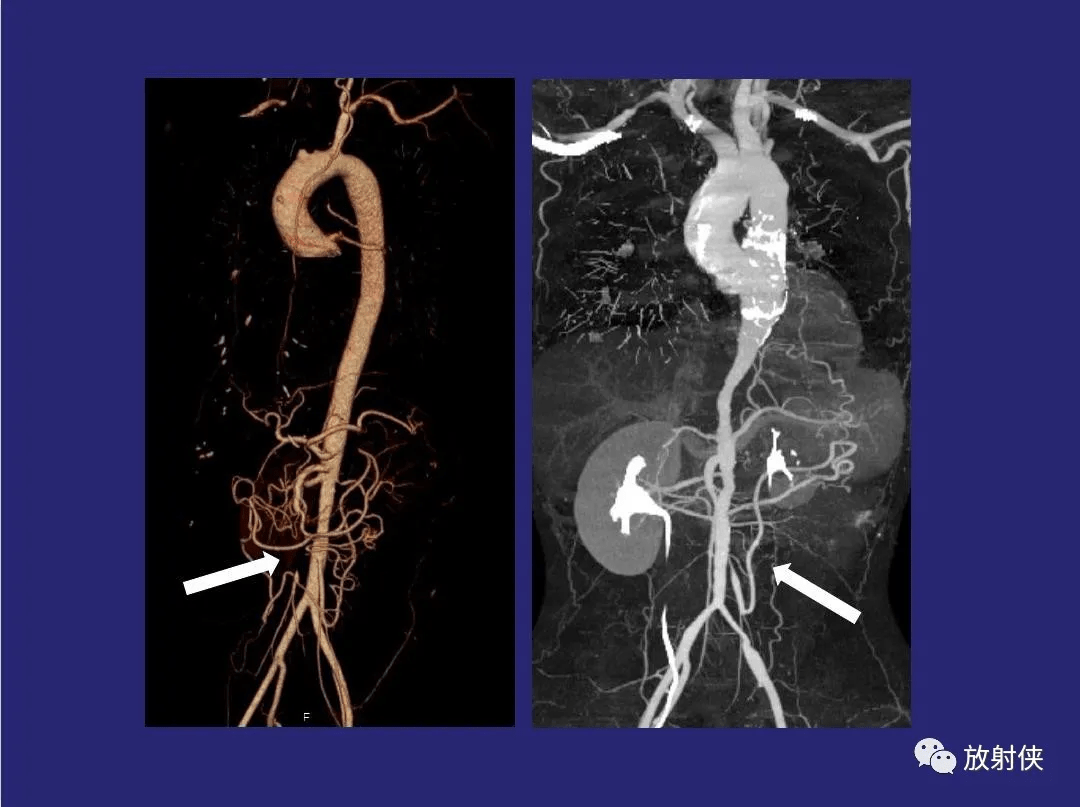

精品大动脉炎分型及ct诊断

图片尺寸1076x809